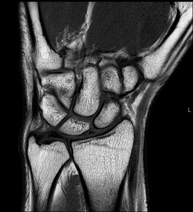

- Wrist / carpus MRI

Examination to study injuries to tendons, muscles and joints. Very useful for assessing minor, otherwise unnoticed fractures, ligament injuries, and inflammatory and degenerative processes (arthritis and osteoarthritis). It lasts approximately 20 minutes. It is a radiation-free procedure.

- Wrist MRI arthrography

Examination to study injuries to small anatomical structures in joints, such as ligaments and cartilage. Prior to the examination, a contrast fluid is injected into a joint, guided by X-ray imaging. The total duration of the two procedures is 50 minutes.